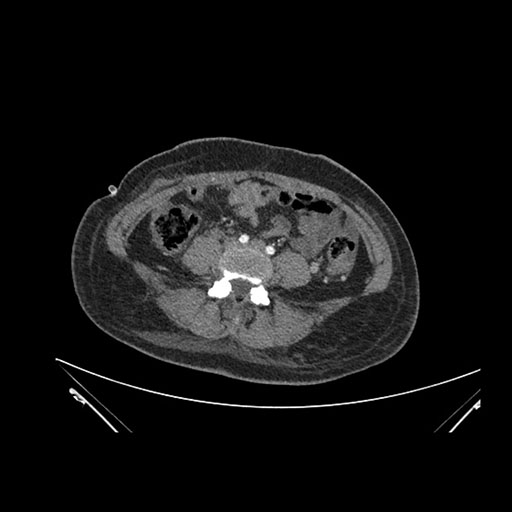

Imaging Analysis

Look through the patient's CT scan to identify any areas of concern for the necessary procedure.

Coronal Venous

Based on initial findings, which issue(s) would you be most concerned about?